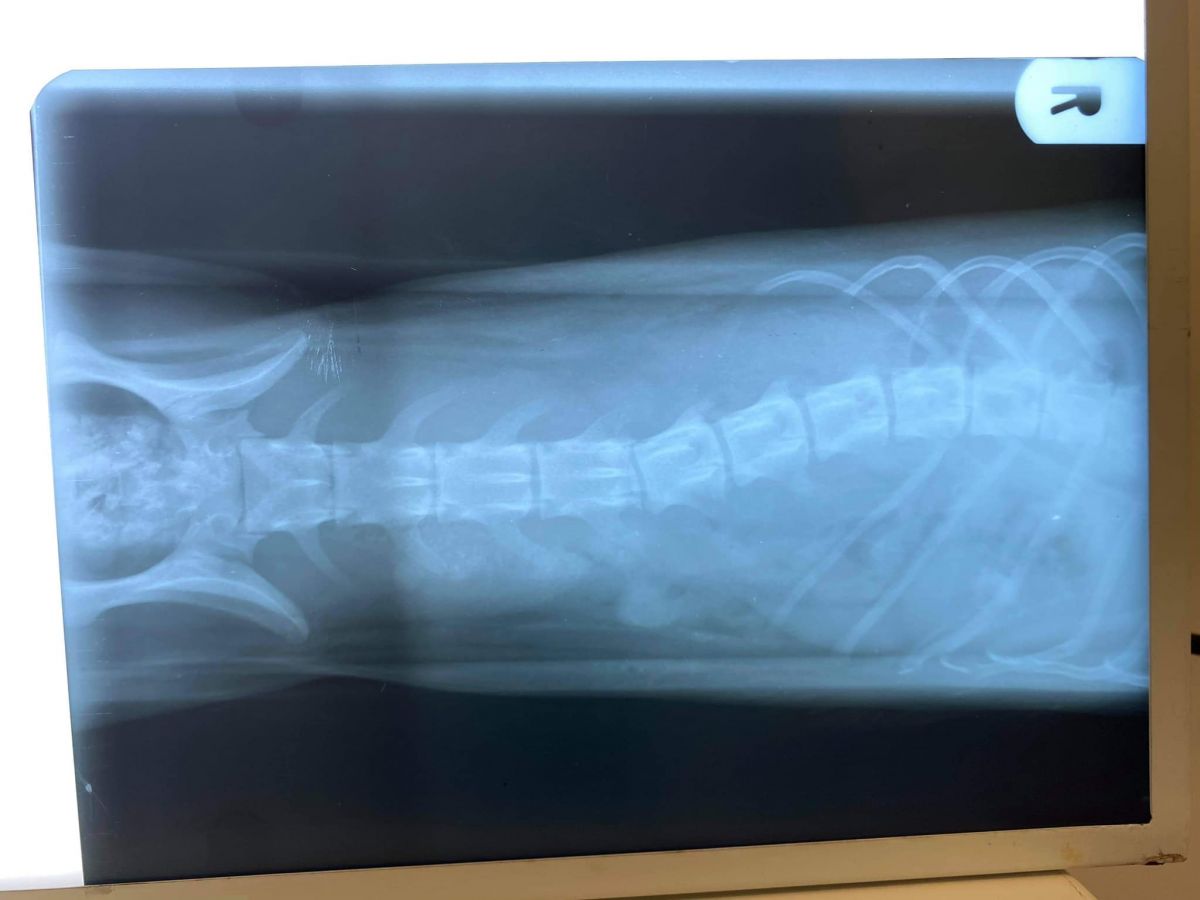

”Am reușit să o stabilizăm iar starea ei este una  bună acum, însă din păcate în urma radiografiilor prezintă o deplasare vertebrală, motiv pentru care momentan este paralizată”,

O intervenție de neuro-chirurgie de fixare a corpurilor vertebrale afectate i-ar da șansa unei vieți normale, să poată să meargă din nou.